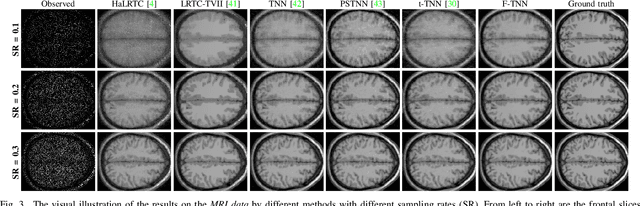

Abstract:In this paper, we study multi-dimensional image recovery. Recently, transform-based tensor nuclear norm minimization methods are considered to capture low-rank tensor structures to recover third-order tensors in multi-dimensional image processing applications. The main characteristic of such methods is to perform the linear transform along the third mode of third-order tensors, and then compute tensor nuclear norm minimization on the transformed tensor so that the underlying low-rank tensors can be recovered. The main aim of this paper is to propose a nonlinear multilayer neural network to learn a nonlinear transform via the observed tensor data under self-supervision. The proposed network makes use of low-rank representation of transformed tensors and data-fitting between the observed tensor and the reconstructed tensor to construct the nonlinear transformation. Extensive experimental results on tensor completion, background subtraction, robust tensor completion, and snapshot compressive imaging are presented to demonstrate that the performance of the proposed method is better than that of state-of-the-art methods.